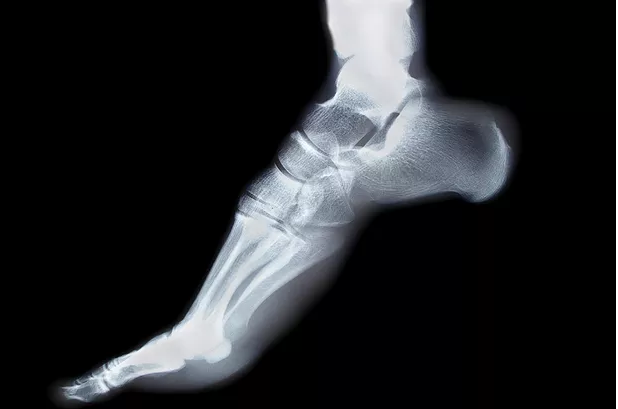

The human foot is made up of 26 bones. If you include the sesamoid bones, then there are 28 bones in the human foot. The sesamoid bones are the two tiny little bones found underneath the ball of the big toe. These bones are often excluded when counting foot bones.

The tarsus, metatarsus, and phalanges constitute the skeleton of the foot. In the rear part of the foot, you have the talus and the calcaneus. Moving forward from there, you will find the 3 cuneiform bones, and the cuboid. In the middle, you will find the navicular and towards the front you will find the metatarsals. After the metatarsals come the phalanges which are found in the toes.

All these bones fit neatly together to create three arches of the foot. The medial longitudinal arch, the lateral longitudinal arch and anterior transverse arch.